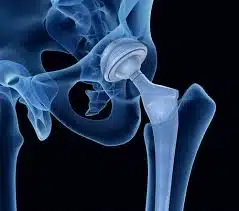

الهدف الأساسي لجراحة استبدال مفصل الورك هو إزالة مفصل الورك المتضرر واستبداله بمفصل اصطناعي. يتم الصاق المفصل الاصطناعي بعظمة الفخذ، الساق والرضفة. يتكون الجزء الملتصق بعظمة الفخذ من معدن صلب وأملس، والذي يستطيع تحمل أوزان ثقيلة ، في حين أن مفصل الرأس مصنوع من السيراميك. علاوة على ذلك ، فإن الأطراف الصناعية في الورك لها فئتان مختلفتان: الأطراف الاصطناعية والدعامات. طرف اصطناعي غير مدعم متصل بالعظم مع سطح خاص بينما سيتم إرفاق الطرف المدعّم باستخدام الملاط الجراحي. في بعض الأحيان يفضل الجراحون الجمع بين هذين النوعين لاستبدال الورك.

كيف يتم إجراء جراحة استبدال مفصل الورك؟

في جراحة استبدال مفصل الورك ، يقوم الجراح باستبدال الطرف العلوي من عظمة الفخذ بكرة مصنوعة من المعدن، وإعادة طلاء تجويف مفصل الفخذ، الذي يقع في الحوض بقشرة معدنية مغلفة بطبقة من البلاستيك. رأس الفخذ هو أعلى جزء من عظمة الفخذ وهو مستدير كروي. عندما يتضرر مفصل الورك من التهاب المفاصل أو الروماتيزم أو لأسباب أخرى ، تحدث الكسور عادة في كل من العظام على شكل وعاء في تجويف الحوض ورأس الفخذ. يقوم الطبيب بتقليم الحافة الغضروفية باستخدام طعوم خاصة، أي إزالة الغضروف المتبقي والعظام الإضافية من التجويف ليشكل نصف كروي كامل.